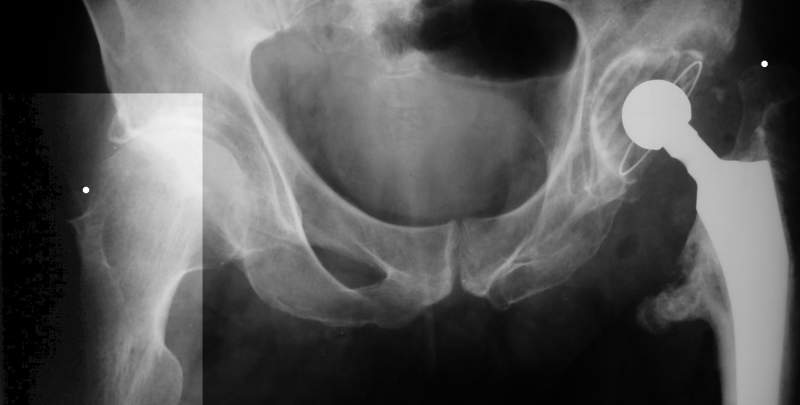

Больного прооперировали на прошлой неделе (цементный протез, цемент с гентамицином). Использовали задне-боковой доступ. В области перелома подвижности практически не было, так что тему сообщения уместно заменить на "неправильно сросшаяся шейка". И в головке, и во впадине

были значительные дегенеративные изменения, так что ни биполяр, ни остеосинтез тут неуместны (хотя это предлагали в ortopod'е). После релиза удлинили ногу на 3 см. Дальше удлинять побоялись из-за

натяжения седалищного нерва, хотя в принципе можно было бы еще 15-20 мм нарастить. По послеоперационной рентгенограмме анатомическое укорочение порядка 15 мм. Клинически при ходьбе - 4 см, но это за счет перекоса таза.

The patient underwent cemented THR on last week. Postero-lateral approach was used. There was only minimal motion at the fracture site and we had to cut the femoral head with oscillating saw. The femoral head was deformed with it's cartilage completely absent in some areas.

Acetabulum showed gross degenerative changes, especially in superior rim. So I think it was right choice not to do ORIF in this case. After some soft tissue release we've lengthened the leg up to 3 cm. Further lengthening was possible but we stopped at that moment due to tension of n. ischiadicus. Now patient walks with crutches. Leg length discrepancy is about 4 cm due to pelvic tilt (discrepancy on post-op x-ray is 15 mm).